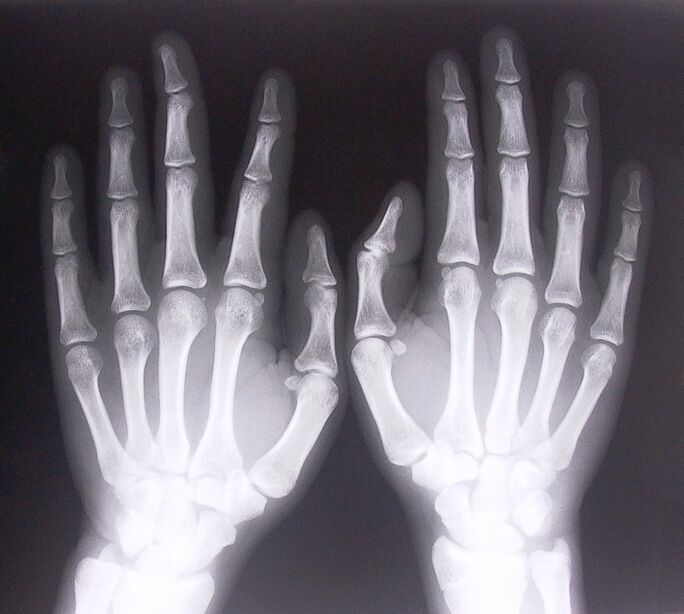

- Stenosing ligamentitis.To identify the cause of the disease, it is necessary to undergo an x-ray.Symptoms are typical: painful hand movement, tight palm curl.Also, when expanding, clicks are usually heard.

To start treating finger joint pain, you need to correctly determine what disease caused it.To determine what kind of disease affects a person who feels pain in the joints when bending their arms, doctors recommend following the following procedures:

- Take x-rays.